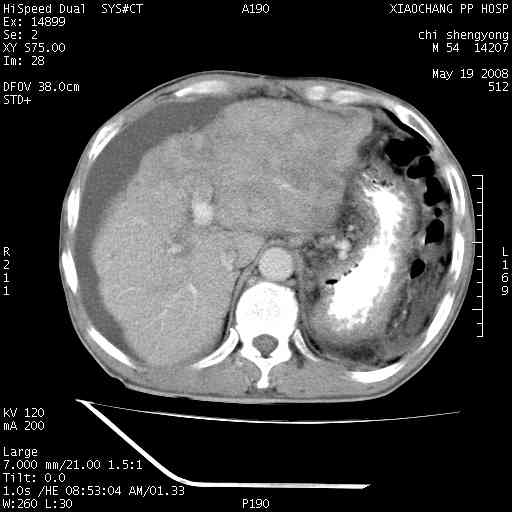

以下是引用zjzjr在2008-5-21 10:52:00的发言:[br]肝左叶巨块型肝癌伴门静脉左支瘤栓形成.肝硬化、腹水,胃底静脉曲张,脾术后改变。

以下是引用随光逐影在2008-5-21 16:20:00的发言:[br]1)肝左叶肝癌伴门静脉左支瘤栓形成,腹膜后淋巴结转移。2)肝硬化、腹水、胃底静脉曲张。3)胆囊炎。4)脾脏缺如,为切除术后所致。